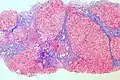

Micrograph showing cirrhosis, trichrome stain

The gold standard for diagnosis of cirrhosis is a liver biopsy. This is usually carried out as a fine-needle approach, through the skin (percutaneous), or internal jugular vein (transjugular).[92] Endoscopic ultrasound-guided liver biopsy (EUS), using the percutaneous or transjugular route, has become a good alternative to use.[93][92] EUS can target liver areas that are widely separated,[94] and can deliver bi-lobar biopsies.[93] A biopsy is not necessary if the clinical, laboratory, and radiologic data suggest cirrhosis. Furthermore, a small but significant risk of complications is associated with liver biopsy, and cirrhosis itself predisposes to complications caused by liver biopsy.[95]

Once the biopsy is obtained, a pathologist will study the sample. Cirrhosis is defined by its features on microscopy: (1) the presence of regenerating nodules of hepatocytes and (2) the presence of fibrosis, or the deposition of connective tissue between these nodules. The pattern of fibrosis seen can depend on the underlying insult that led to cirrhosis. Fibrosis can also proliferate even if the underlying process that caused it has resolved or ceased. The fibrosis in cirrhosis can lead to destruction of other normal tissues in the liver, including the sinusoids, the space of Disse, and other vascular structures, which leads to altered resistance to blood flow in the liver, and portal hypertension.[96]

As cirrhosis can be caused by many different entities that injure the liver in different ways, cause-specific abnormalities may be seen. For example, in chronic hepatitis B, there is infiltration of the liver parenchyma with lymphocytes.[96] In congestive hepatopathy there are erythrocytes and a greater amount of fibrosis in the tissue surrounding the hepatic veins.[98] In primary biliary cholangitis, there is fibrosis around the bile duct, the presence of granulomas and pooling of bile.[99] Lastly in alcoholic cirrhosis, there is infiltration of the liver with neutrophils.[96]

Macroscopically, the liver is initially enlarged, but with the progression of the disease, it becomes smaller. Its surface is irregular, the consistency is firm, and if associated with steatosis, the color is yellow. Depending on the size of the nodules, there are three macroscopic types: micronodular, macronodular, and mixed cirrhosis. In the micronodular form (Laennec's cirrhosis or portal cirrhosis), regenerating nodules are under 3 mm. In macronodular cirrhosis (post-necrotic cirrhosis), the nodules are larger than 3 mm. Mixed cirrhosis consists of nodules of different sizes.[100]